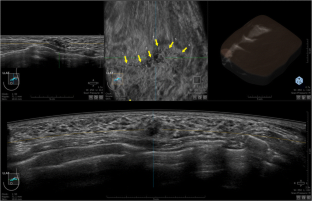

Fig. 3